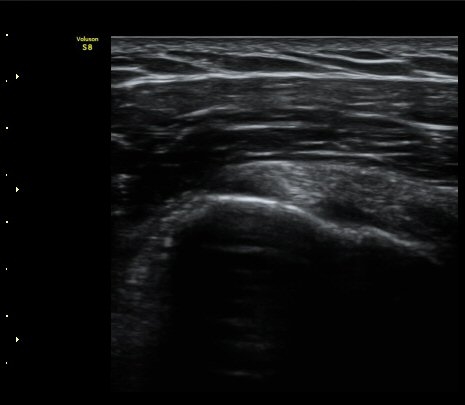

±Ø»ó°Ç Á¾´Ü¸é°Ë»ç¿¡¼­ ´ë°áÀý °Ç ºÎÂøºÎ¿¡ Àú¿¡ÄÚ °Ç °á¼ÕÀÌ °üÂûµÊ

(focal hypoechoic defect of ssupraspinatus tendon at greater tuberosity with

longitudinal scan of subscapularis tendon) »çÁø 4, 5, 6